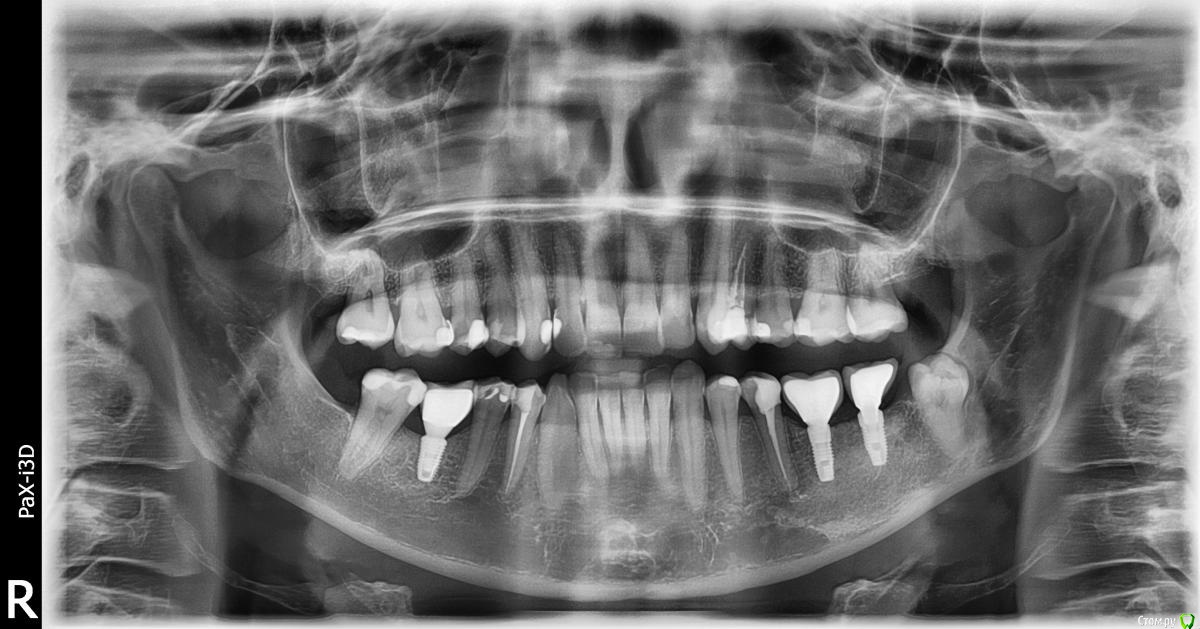

Taste of Honey Опубликовано 17 июня, 2015 Автор Поделиться Опубликовано 17 июня, 2015 (изменено) Сделала панорамный снимок - вроде бы качественный.Посмотрите, пожалуйста, что у меня неладно с левой верхней четверкой, которая реагирует на горячее (запломбирован канал)?И, если можно, правую нижнюю пятерку... тоже реагирует, но на холодное. Большое спасибо! Изменено 17 июня, 2015 пользователем Taste of Honey 1 Ссылка на комментарий